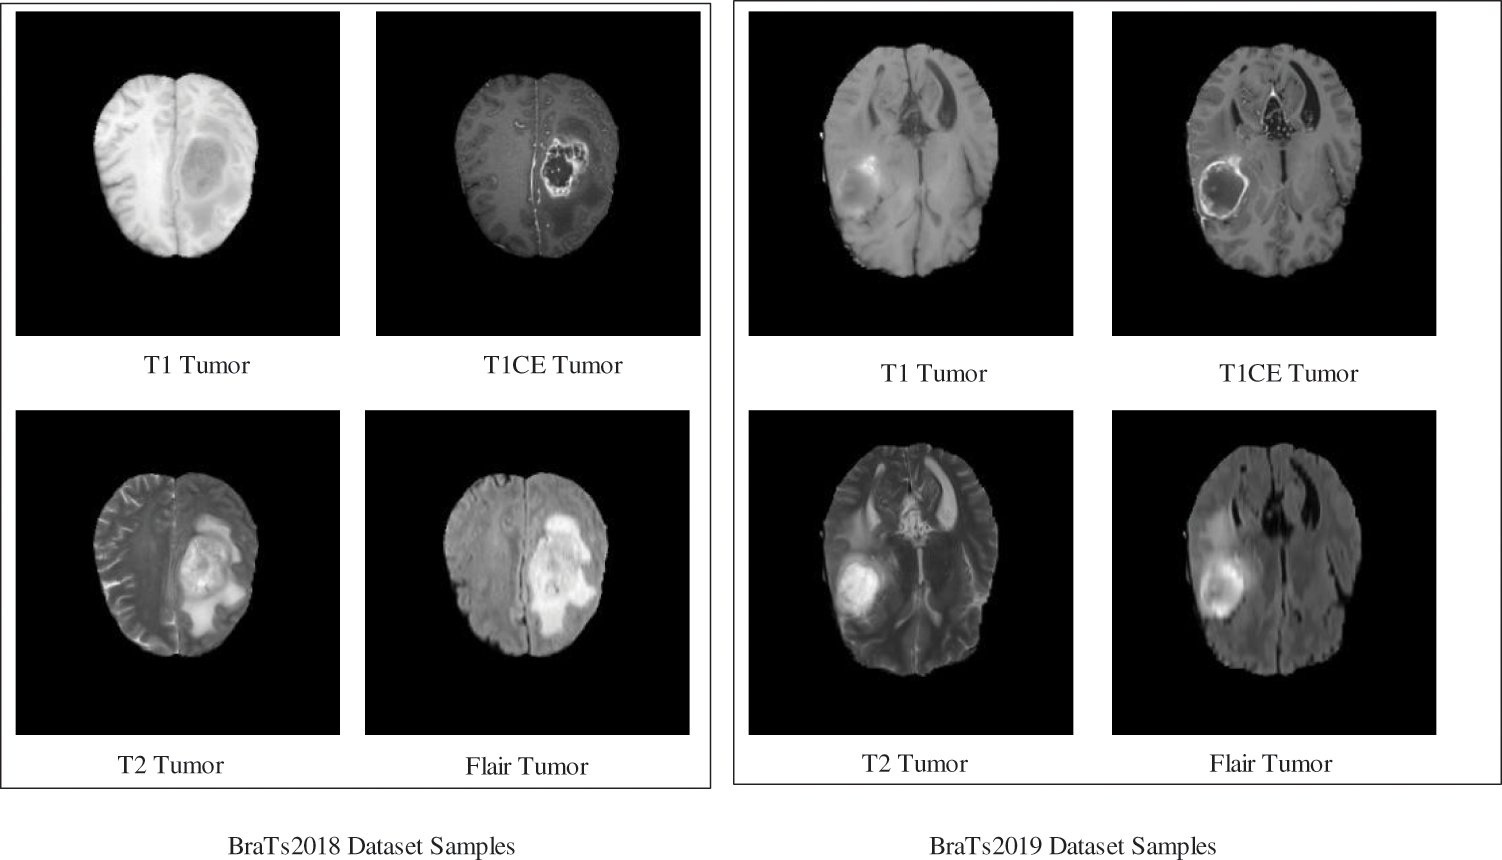

In this work, two datasets–BraTs2018 and BraTs2019, are employed for the experimental process. Both datasets consist of four types of tumor classes such as T1, T1W, T2, and FLAIR.

BraTs2018 [31]: This dataset consists of 385 scans for training and 66 scans for its validation. All the MRI scans of this dataset have a volume of

Figure 2: Sample brain tumor images

BraTs2019 [32]: This dataset consists of 335 scans for training, and validation scans are the same as Brats2018. Four sequences-T1, T1CE, T2, and FLAIR tumors are contained for each volume. Similar to the BraTs2018 dataset, the ground truths are generated manually with the help of expert neuroradiologists. All the MRI scans of this dataset have a volume of

In this work, we utilized 48,000 MRI samples from the BraTs2018 dataset (12,000 in each class), whereas for BraTs2019, the total extracted samples tally 56,000 (14,000 in each class). Initially, the extracted MRI samples had a dimension of